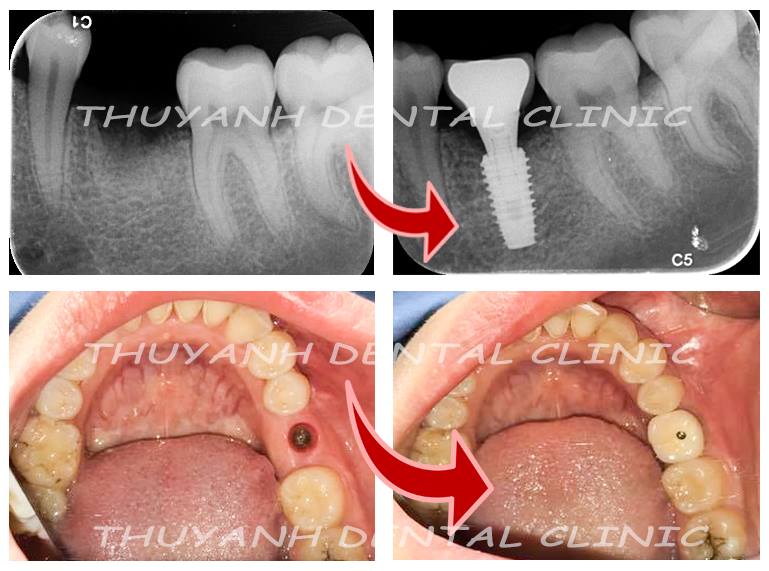

Với sự tiến bộ của y khoa nói chung và nha khoa nói riêng, ngày nay khi một chiếc răng bị sâu nha sĩ sẽ cố gắng điều trị để giữ nó lại và bảo vệ bằng 1 bụp răng sứ. Khi mất răng thì sẽ có phương pháp điều trị phục hình mà nổi bật hiện nay là phương pháp cắm chân răng nhân tạo implant.

Cấy implant là phương pháp trồng răng tốt nhất hiện nay. Implant gồm có 3 phần, phần thứ nhất là chân răng, được cấy thẳng vào xương hàm thay thế chân răng mất. Phần thứ 2 là trụ phục hình abutment đó là phần kết nối với chân răng và nhô lên khỏi lợi để răng sứ bọc lên đó. Phần thứ 3 là răng sứ, sẽ là 1 chụp sứ hoặc hàm giả gắn lên abutment.

Bước đầu tiên trong quá trình cắm chân răng nhân tạo implant là khám tổng quát. Bác sĩ sẽ khám thực tế trên miệng để xác định rõ tình trạng mất răng và đưa ra cho bệnh nhân phương pháp phục hình răng phù hợp nhất.